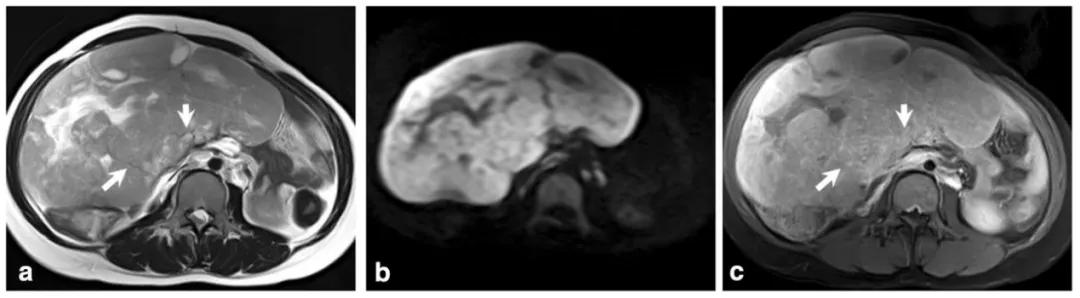

女,18 岁,卵黄囊瘤(右侧),AFP 升高。T2WI 示卵巢实性为主肿物(图 a),内见低信号纤维血管分隔(白箭),实性成分 DWI 呈高信号(图 b),增强扫描明显强化(图 c),内见无强化坏死区(箭头)。